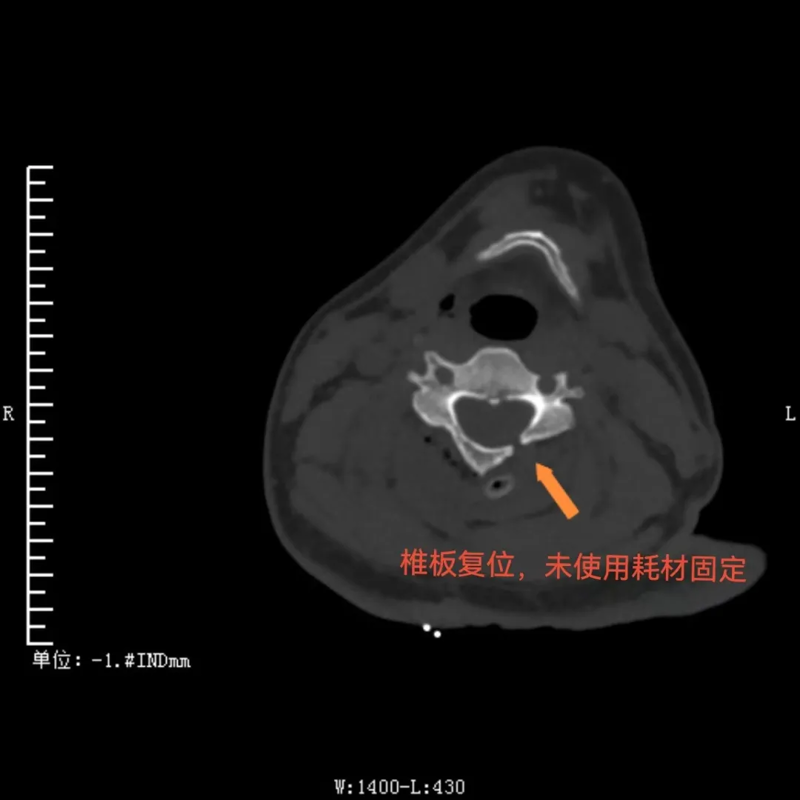

与传统手术需要完全切除肿瘤节段全椎板不同,这种新的手术方式术后仅需将掀起的椎板纳还并以丝线固定即可,无需使用金属连接耗材固定。这不仅使得复位效果更佳,而且患者在术后复查CT、磁共振时无金属伪影干扰,让检查结果诊断更准确,还为患者节省了相当大的一笔费用。

椎板复位,未使用耗材固定,为患者节省费用